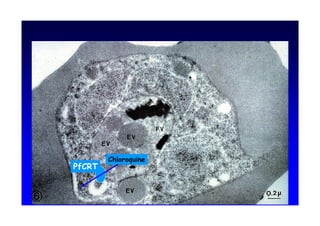

3I57               Vacuole digestive

3I57 Vacuole digestive + = U« Y H UV H X UV